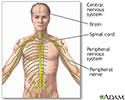

Central nervous system and peripheral nervous system - illustration

Central nervous system and peripheral nervous system

illustration

Central nervous system and peripheral nervous system - illustration

Central nervous system and peripheral nervous system

illustration